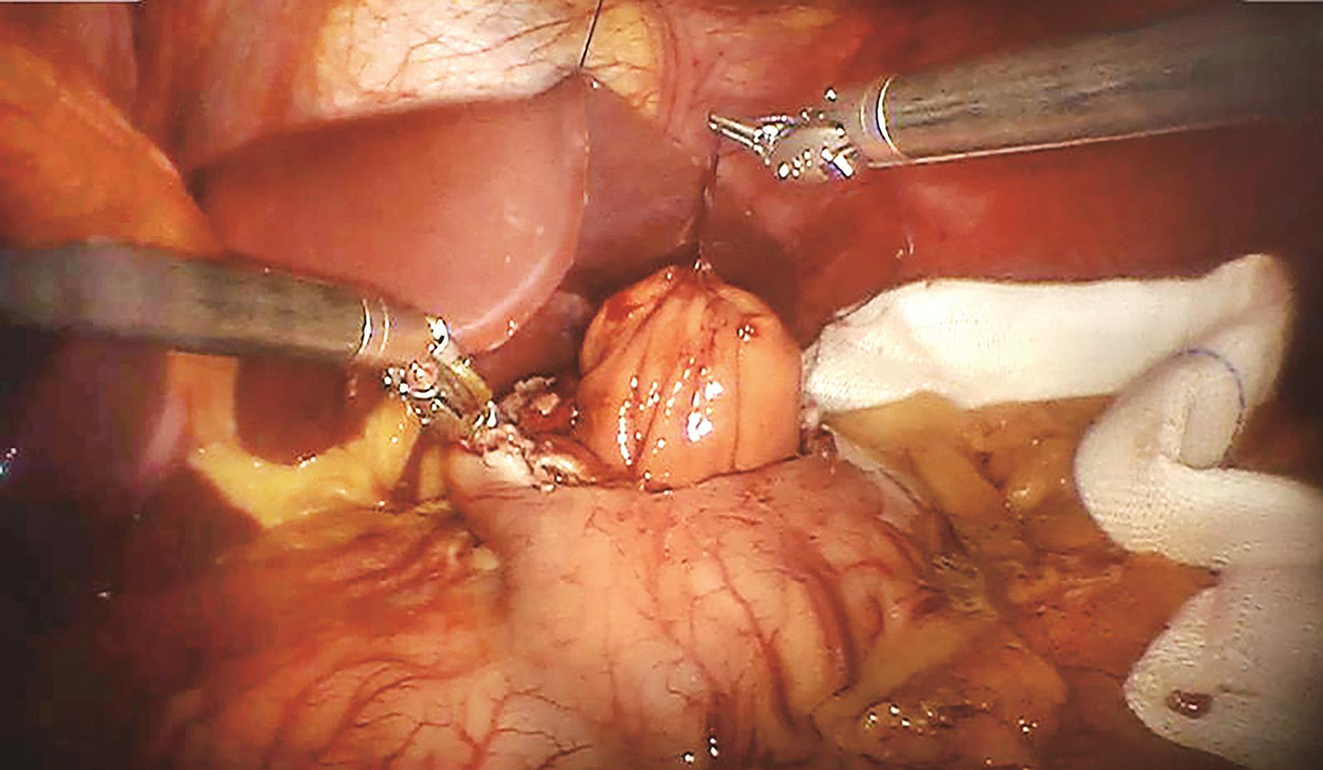

患者于加速康复外科(enhanced recovery after surgery,ERAS)理念指导下行术前准备,2016年9月27日行“机器人辅助下腹腔探查术+胃肿瘤切除术”。术中先行胃镜探查发现肿瘤位于胃底后壁近贲门处,大小约2.0cm×1.0cm;离断大弯侧网膜,暴露胃后壁瘤体,切开后壁肿瘤所对应胃前壁,以腹腔镜下切割吻合器于距离瘤体1cm处离断胃壁,完整切除肿瘤,将肿瘤置入标本袋中并用丝线结扎袋口,经绕脐半周切口取出,检查标本切缘安全,以可吸收线加固切口,缝合腹部戳孔及绕脐切口。手术过程顺利,手术时间60min,术中出血量约为10ml(图2~图5)。

图3 丝线提起肿瘤